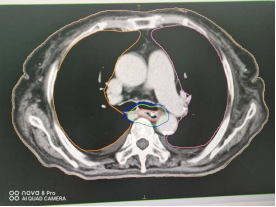

1、肺癌横断面及矢状面肿瘤处治疗剂量显示图

2、咽部肿瘤横断面及矢状面治疗剂量显示图

3、计划系统效果图:黄色线内-蓝色线外深颜色区域为高剂量区域,黄色线外及蓝色线内为低剂量区域。即照射剂量区域可按肿瘤治疗的需要进行调节。